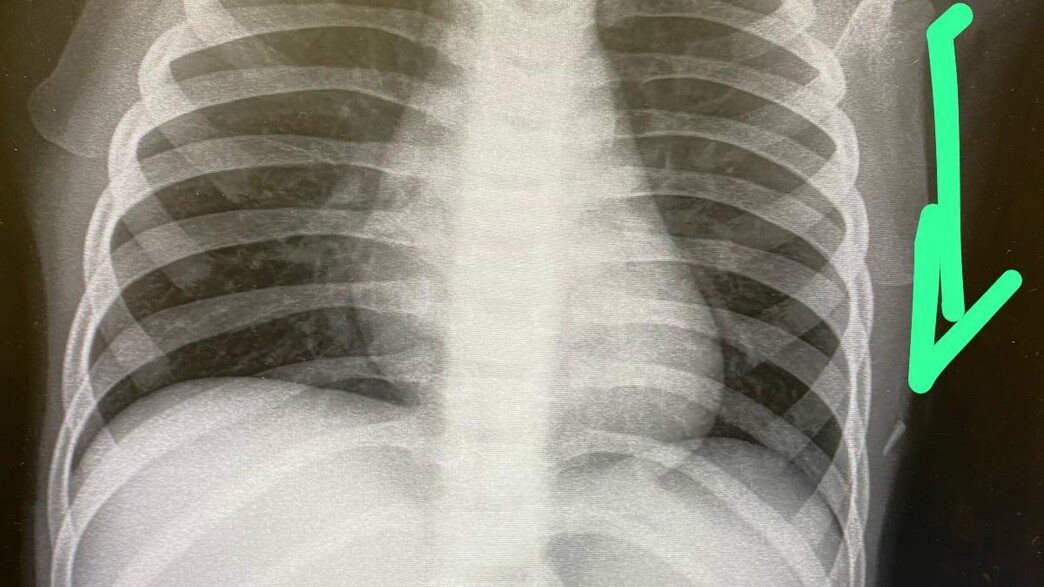

ד"ר ודים קפולר, מנהל יחידת כירורגיה ילדים בבית החולים הציבורי אסותא אשדוד שקיבל אותה לטיפול, מספר כי במקום נעשה לה צילום נוסף ובאמצעותו הבחינו הרופאים בעצם זר תת-עורי באזור בית החזה, ככל הנראה חוד של עט. העצם הזר הוצא תחת טשטוש.